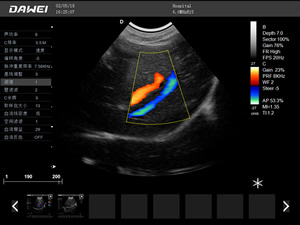

·支持彩色多普勒、頻譜多普勒、能量多普勒、連續多普勒等成像技術

彩色多普勒動物超聲診斷儀